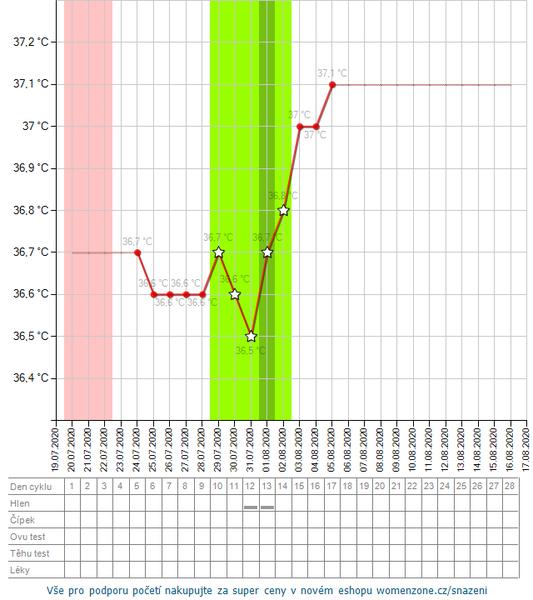

Ahojte. Prosím poradite mi ešte trošku? 2.8. som dostala ms, iba také malé splnenie, ďalší deň už to vyzeralo normálne, včera už slabšie a dnes už len spinim. Ide mi však o teplotu. Zaznacila som si 2.8. ako nový cyklus, avšak teplota mi vôbec neklesla pod ciaru. Dala som to aj dokopy bez zapisania ms, aby ste to lepšie videli na grafe. Myslite, že moze ísť o nejaký zápal, ale sa to je to normálne a predovulacna teplota môže byť v novom cykle kúsok vyššia? Cítim sa tak zľahka choro, trošku dutiny, únava a vyčerpanie.

@majka_3 naposledy 13 DPO a bol negatívny. Nemyslím si, že by išlo o tehotenstvo. Toho 3.8. bolo konečne normálne silne krvácanie. Teda nie úplne ako som mávala predtým, ale oproti posledným ms od potratu som teraz mala naozaj normálnu ms. Skôr sa bojim či nejde o nejaký zápal, infekciu, či nejakú poruchu..